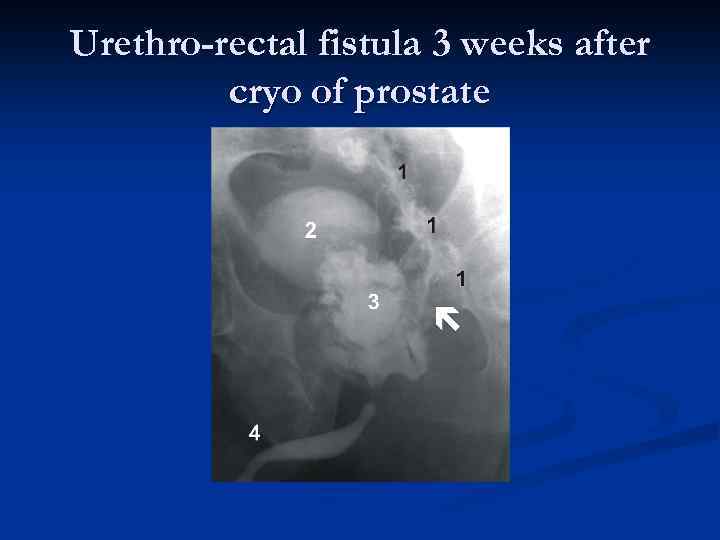

Urethro-rectal fistula 3 weeks after cryo of prostate

Urethro-rectal fistula 3 weeks after cryo of prostate